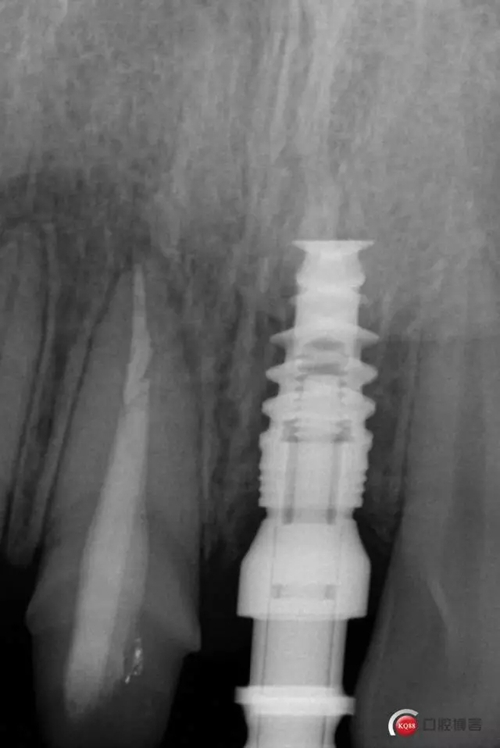

藻酸鹽對(duì)頜取模,超硬石膏灌注。發(fā)加工廠,與技工溝通注意事項(xiàng),等修復(fù)體做好后,檢查模型。是否就位,是否密合,預(yù)約患者復(fù)診戴牙,消毒修復(fù)區(qū),旋出愈合基臺(tái),定位器指導(dǎo)安放修復(fù)基臺(tái),試戴冠,調(diào)磨鄰接及 咬合至合適,拋光,患者滿意,加力扳手加力至30N,拍X片見就位良好,特芙蓉及暫封膏封中央螺絲孔,聚羧酸鋅粘固劑粘固,或是樹脂水門汀粘固,清理多余粘結(jié)劑,光固化樹脂封螺絲孔,拋光。術(shù)后注意隨訪。